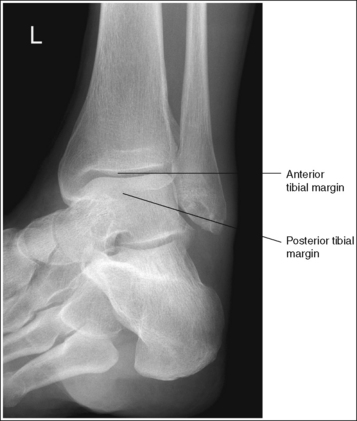

The tibiotalar joint space is open, and the tibia is demonstrated without foreshortening.

• Evaluating the openness of the tibiotalar joint. On an AP ankle projection, determine whether an open joint was obtained and whether the tibia is demonstrated without foreshortening by evaluating the anterior and posterior margins of the distal tibia. On an AP ankle projection with accurate positioning, the anterior margin is demonstrated approximately 0.125 inch (3 mm) proximally to the posterior margin (see Figure 6-48). If the proximal lower leg was elevated or the central ray was centered proximal to the tibiotalar joint, the anterior tibial margin is projected distally, resulting in a narrowed or obscured tibiotalar joint space (see Image 34). If the distal lower leg was elevated or the central ray was centered distal to the tibiotalar joint, the anterior tibial margin is projected more proximally to the posterior margin than on an AP ankle projection, expanding the tibiotalar joint space and demonstrating the tibial articulating surface (see Image 35).

• Evaluating the openness of the tibiotalar joint. On an AP oblique ankle projection, you can determine whether the positioning and central ray alignment goals have been met by evaluating the anterior and posterior margins of the distal tibia. On an AP oblique ankle projection with accurate positioning, the anterior margin should be visualized approximately 0.125 inch (3 mm) proximal to the posterior margin. If the proximal lower leg was elevated or the central ray was centered proximal to the tibiotalar joint, the anterior tibial margin is projected distally, resulting in a narrowed or obscured tibiotalar joint. If the patient's distal lower leg was elevated or the central ray was centered distal to the tibiotalar joint, the anterior tibial margin is projected too far proximal to the posterior margin, expanding the tibiotalar joint space and demonstrating the tibial articulating surface (see Images 39 and 40).